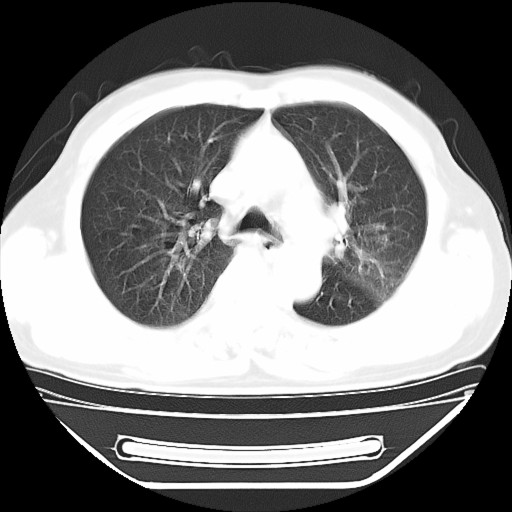

以下是引用hhcckk在2009-5-29 10:34:00的发言:[br]左下肺片絮状边缘模糊影,考虑感染,建议治疗后复查[br]